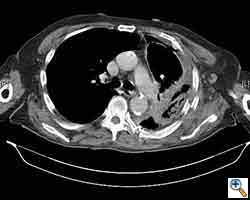

Here we present, as a paradigm of repair, the case of a 65 year old gentleman referred to our institution for an indolent mass in the left anterior chest wall. Repairs for other conditions follow the same rules. This mass had been stable in size for more than 12 months and the patient was prompted to seek medical attention as, after weight loss due to dieting, he felt the mass was uncomfortable while sleeping. Apart from coronary stenting for angina, the past medical history was unremarkable.

Computed tomography scan of the chest showed a mass protruding from the cortex of the third rib. A percutaneous core biopsy was non-diagnostic. We proceeded to an open incisional biopsy. This was reported as showing a spindle cell neoplasm. The patient was therefore scheduled, after multidisciplinary meeting discussion, for radical surgery.

At surgery, the mass was arising from the cortex of the third rib, and solid measuring 5x8 cm. There was no macroscopic involvement of the surrounding extra-thoracic musculature or of the underlying lung, the mass being confined to the rib and intercostal muscles. The patient underwent resection of the second to fourth ribs and the rhomboid muscle as well, in the attempt to get clear margin. The large antero-lateral defect was eventually reconstructed using 2 mouldable titanium bars. To prevent lung herniation through the defect, we reconstructed the layers anatomically using a biological patch (Veritas®). The final histopathology was a low grade sarcoma of the chest wall with clear resection margins.